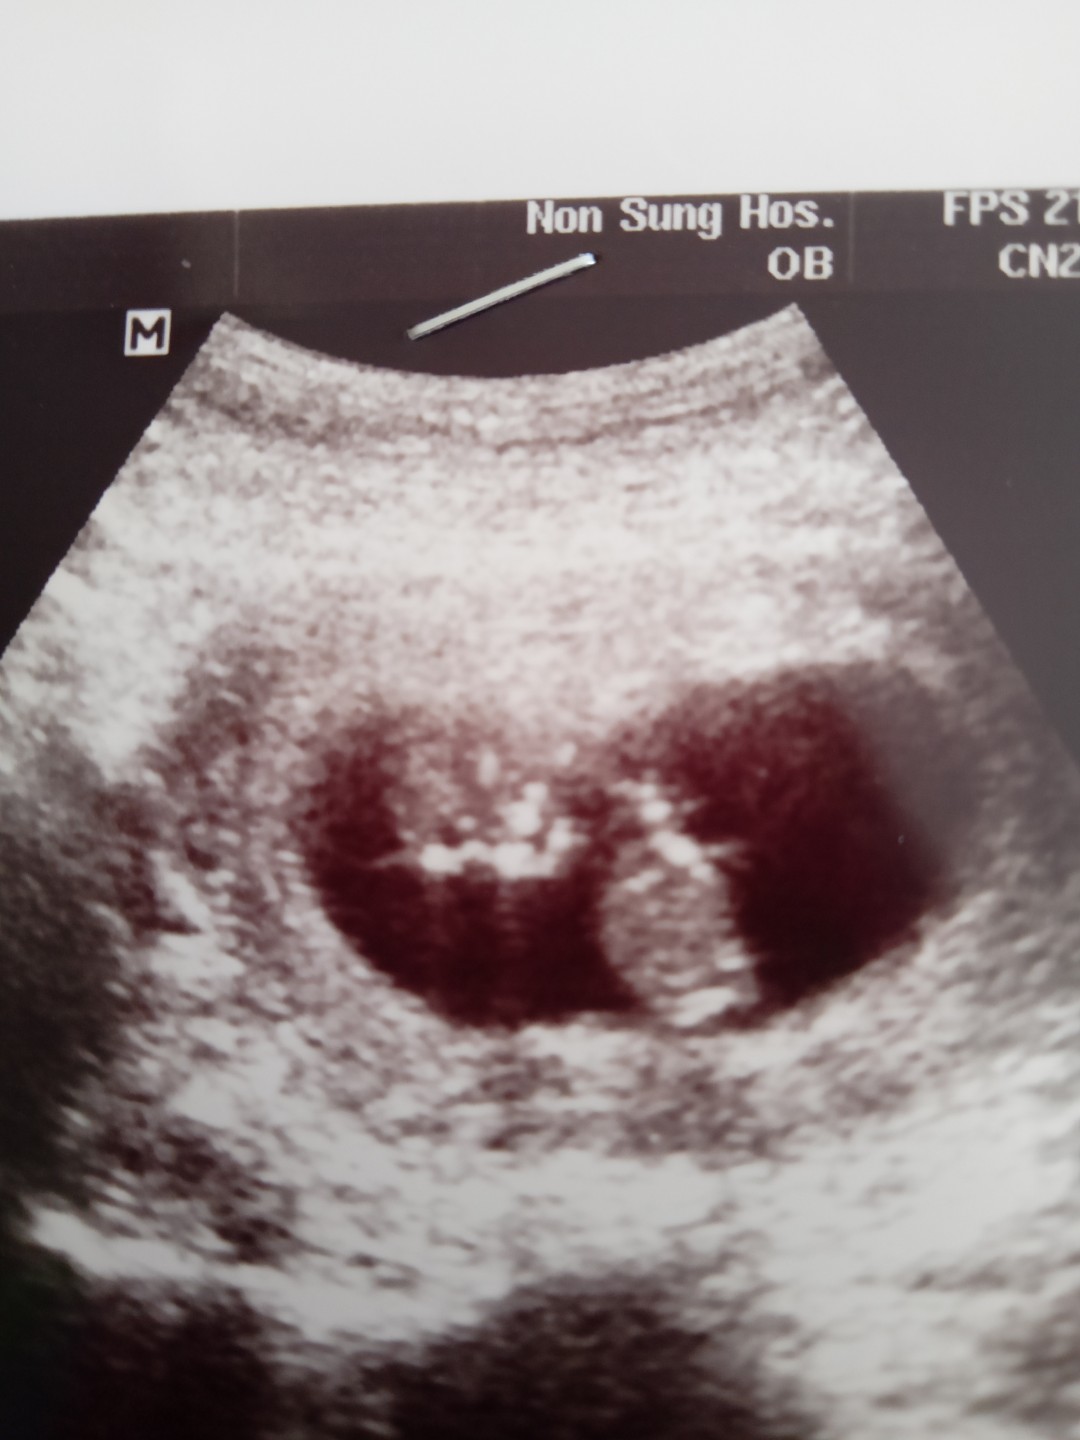

นี่ก็ฝากโรงพยาบาลรัฐนะคะพยาบาลอัลตราซาว์ให้เกือบทุกครั้งค่ะรูปนี้ซาวด์เมื่อวันที่17ก. พ. ค่ะ